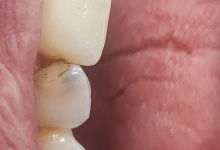

– retractii gingivale cu expunerea radacinilor dentare;

– halena.